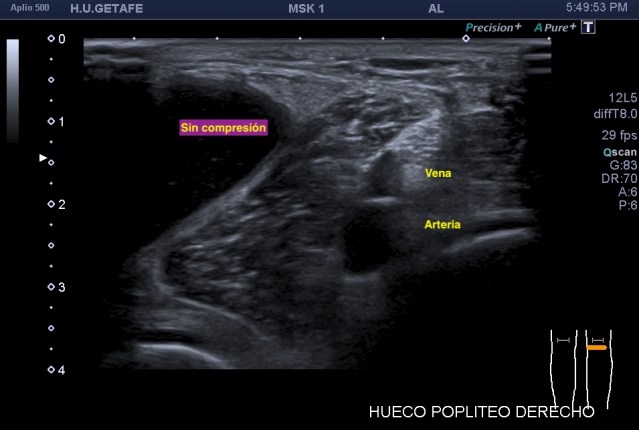

Recuerdo la importancia de comprobar siempre la permeabilidad de los vasos del hueco poplíteo con este tipo de patologías, el parecido de los síntomas de un quiste de Baker roto y la TVP puede ser muy similar y sin embargo, la TVP es una patología potencialmente peligrosa. Para ello pide al paciente que suba la pierna afectada por encima de su otra pierna para poder hacer que el retorno venoso sea más evidente y poder estudiar los mencionados vasos, sobre todo, su vena, claro.

La compresión con la sonda del hueco poplíteo establece la permeabilidad de la vena poplitea. Normalidad por tanto, manda, el comportamiento de la vena, compresible, y no el uso del doppler, por eso me permito el lujo de enseñarte la técnica sin el uso del doppler color. Línea roja: Si la vena no se colapsa.